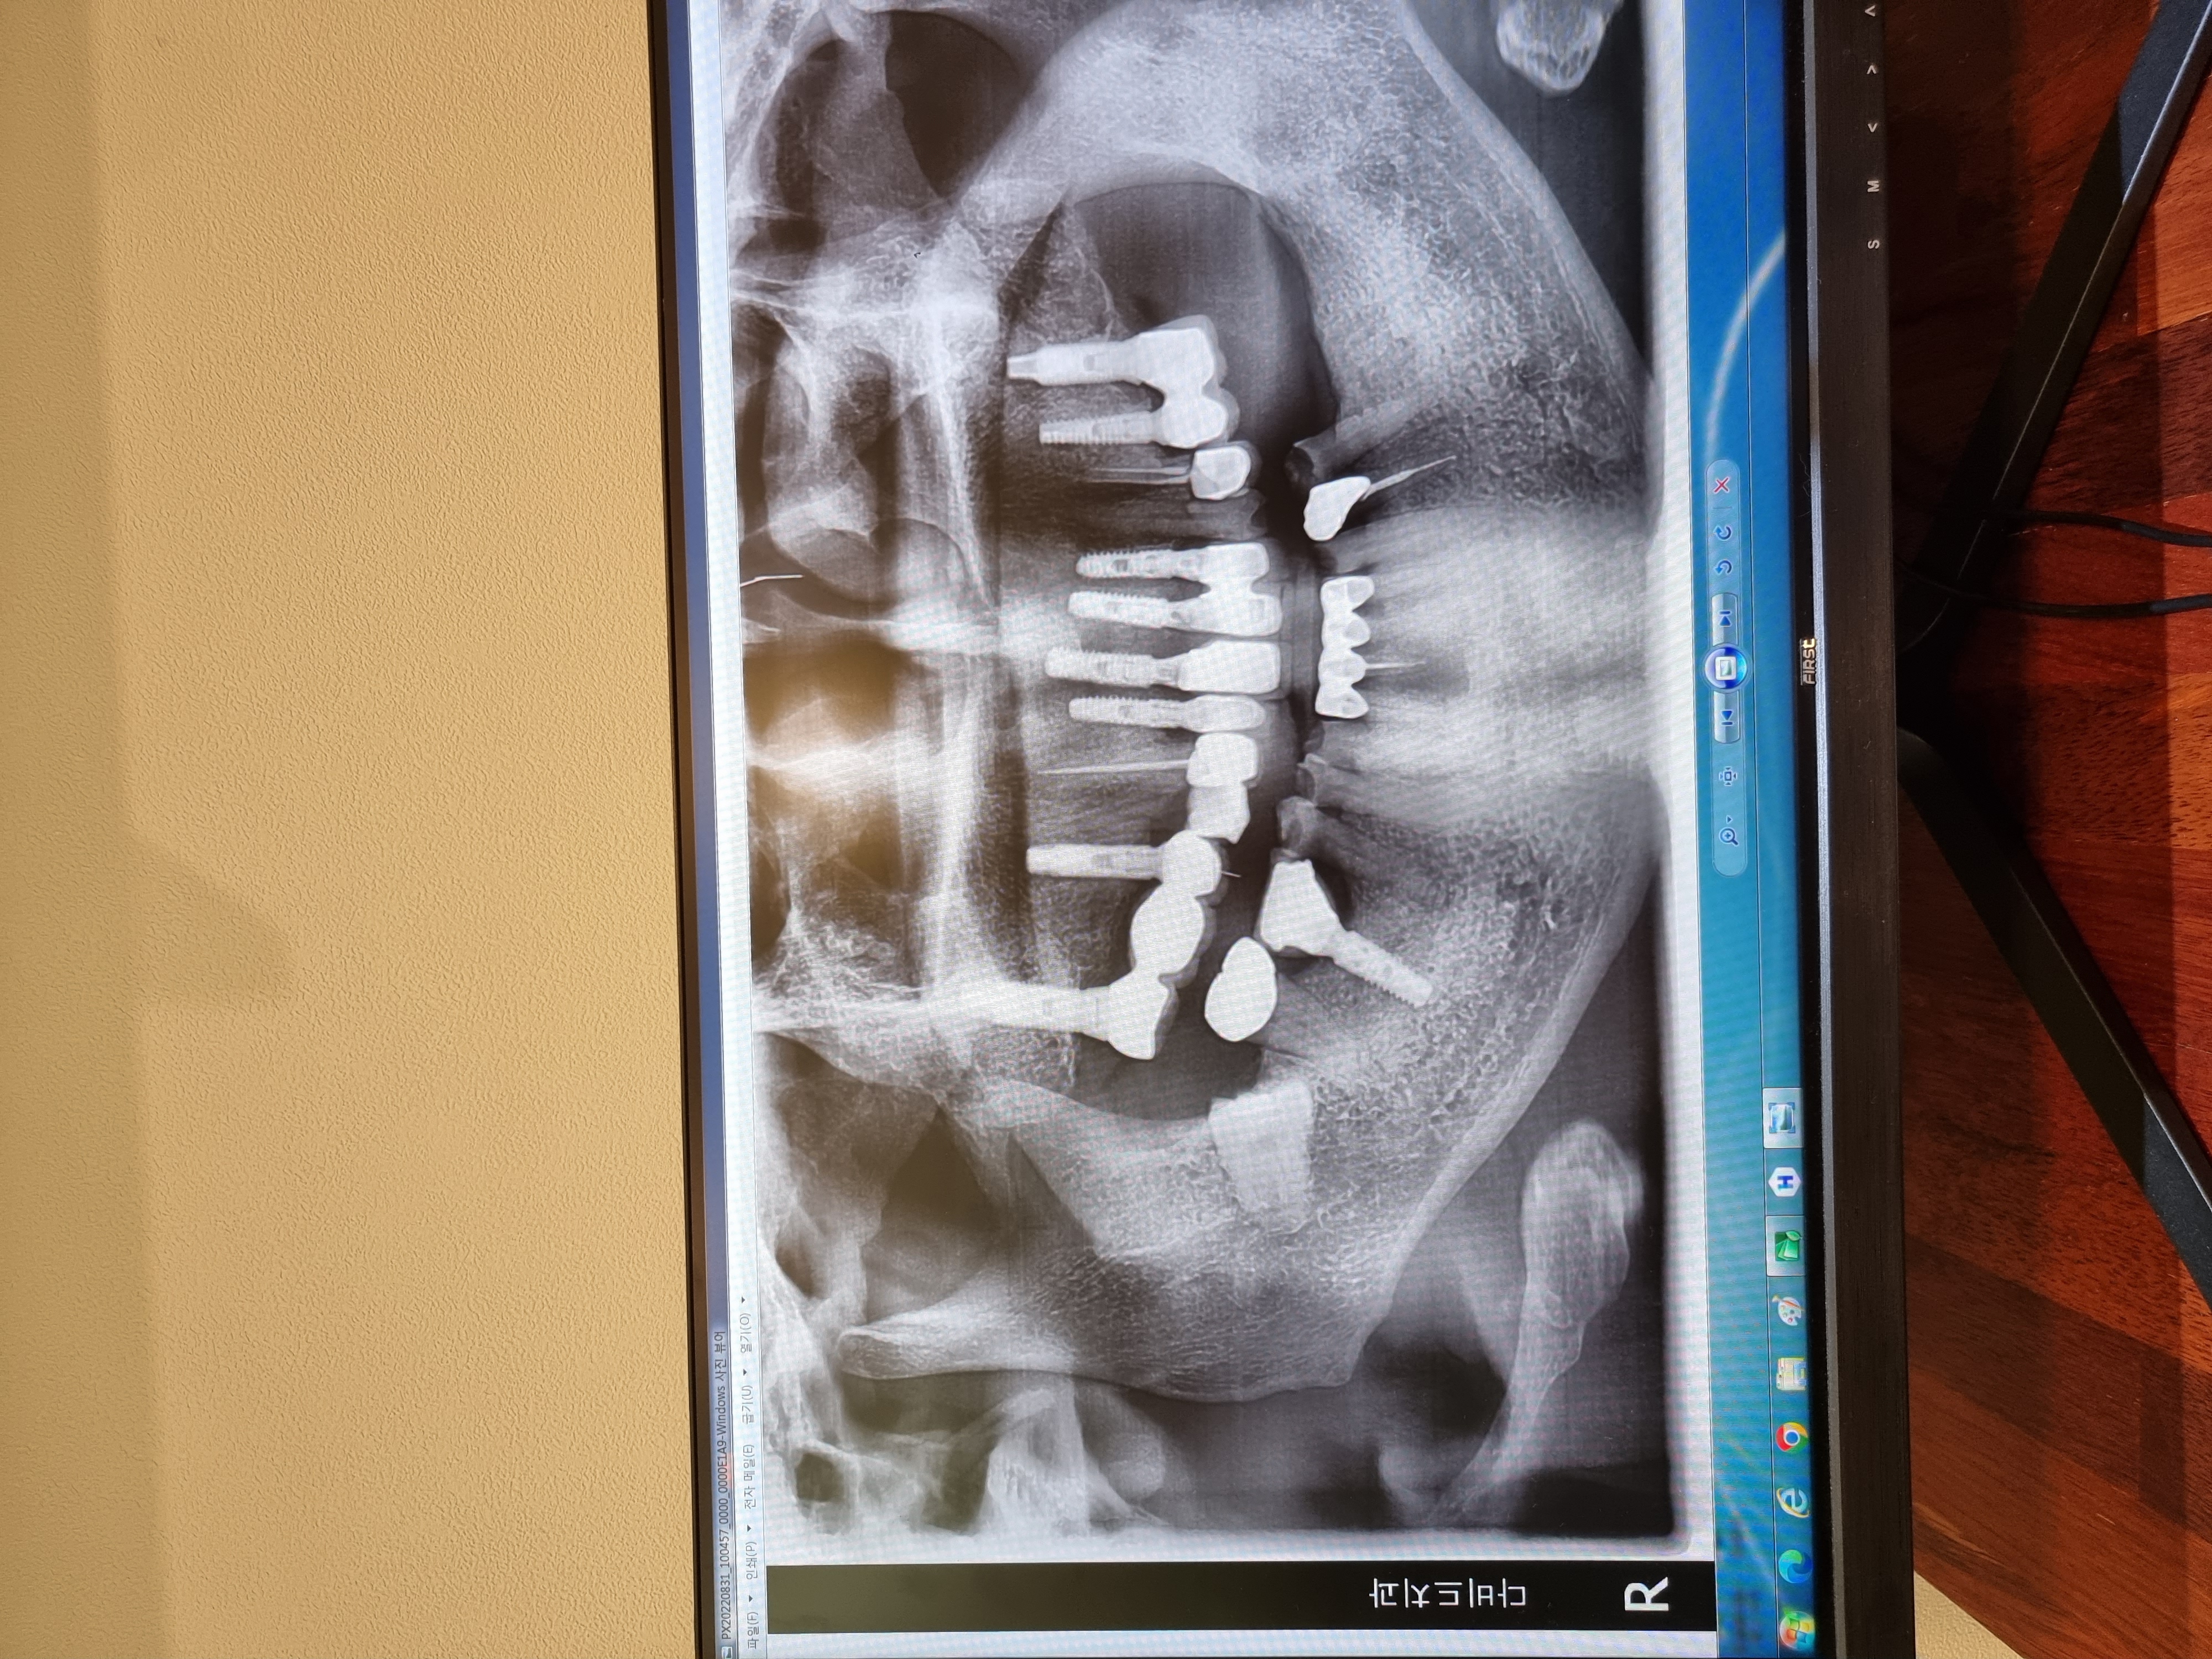

전

후

시술친절하고세밀하게 잘해주셔서감사합니다 다른곳에서도 많이홍보하고싶위서홍보중 너무잘해주십니다